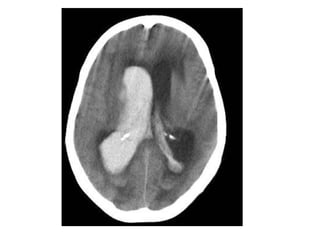

Thrombosis of deep cerebral veins

-The clinical presentation of thrombosis of the

deep cerebral venous system are severe

dysfunction of the diencephalon reflected by

coma and disturbances of eye movements and

pupillary reflexes , usually this results in a

poor outcome

-However , partial syndromes without a decrease in

the level of consciousness or brainstem signs

exist which may lead to initial misdiagnoses

-Deep cerebral venous system thrombosis is an

underdiagnosed condition when symptoms are

mild and should be suspected if the patient is a

young woman , if the lesions are within the basal

ganglia or thalamus and especially if they are

bilateral

Patient with deep cerebral vein thrombosis , notice the bilateral infarctions in

the basal ganglia